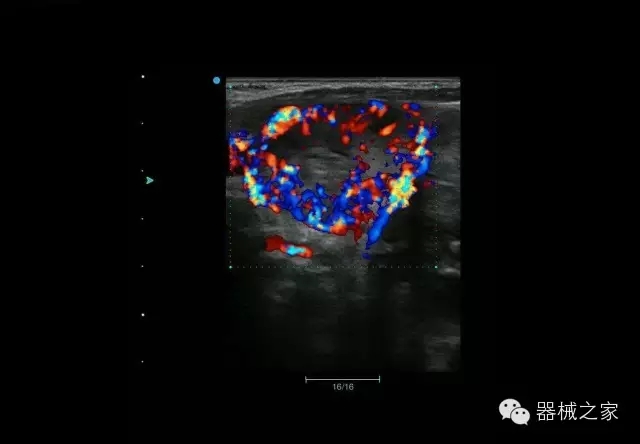

臨床圖片賞析

臍帶血流